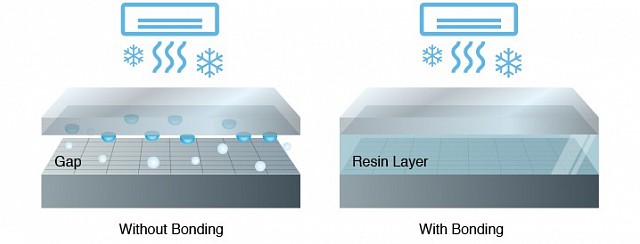

所使用的保护玻璃硬度超过 9H,不易划伤。光学粘合通过在液晶面板和外部玻璃之间的气孔中注入光弹性树脂,进一步提高了物理强度。由于液晶面板和外部玻璃之间没有缝隙,因此可以防止灰尘和湿气对液晶面板造成损坏。

在温度剧烈波动的环境中使用显示器时,液晶面板和保护玻璃之间的气孔中可能会出现冷凝水。使用光学胶合技术后,就不会出现气孔,这意味着不会产生冷凝水,也不会影响可视性。使用的保护玻璃硬度超过 9H,不易划伤。光学胶合技术通过在液晶面板和外部玻璃之间的气孔中注入光弹性树脂,进一步提高了物理强度。由于液晶面板和外部玻璃之间没有缝隙,因此可以防止灰尘和湿气对液晶面板造成损坏。